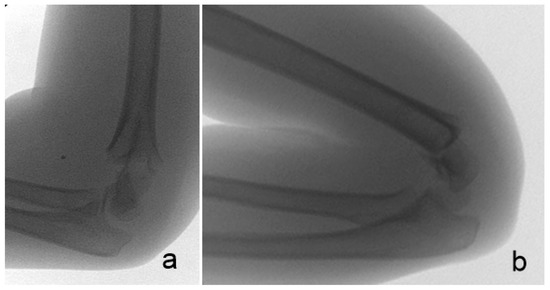

We observed a pediatric supracondylar humeral fracture subtype with sideward translation without any significant sagittal plane displacement on initial radiographs (Figure 1). This fracture is not clearly described by the most often used Gartland classification system.

The radiographic features of the fractures include a significant sideward translation in the coronal plane, usually more than 25% of the distal fragment width, with no or minimal posterior displacement in the sagittal plane. Therefore, the anterior humeral line crosses the capitellum at the middle or the anterior third. In our series, all but one distal fragments were displaced to the radial side (Figure 1).

Figure 1. Radiographs of a sideward displaced supracondylar fracture of the humerus of two patients. Anterior-posterior (AP) and lateral initial radiographs taken in the emergency department. A substantial sideward displacement of the distal fragment on AP view, without any considerable displacement in the sagittal plane, can be observed.